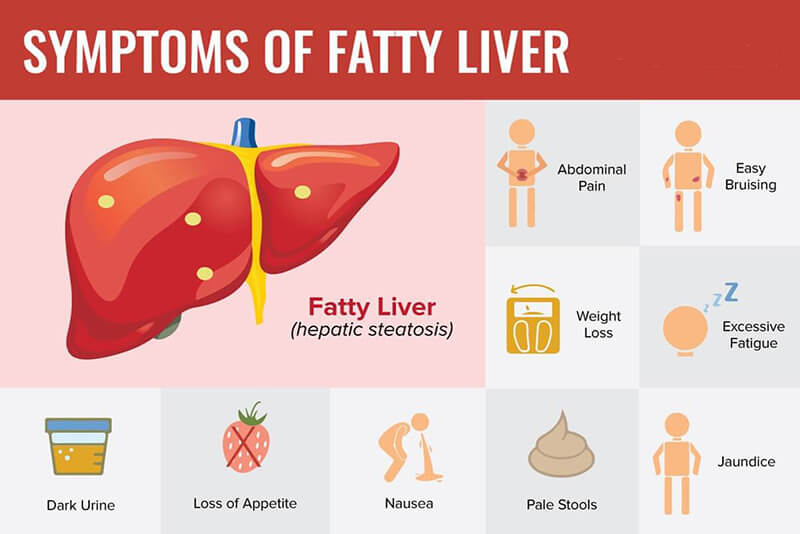

Hepatic Steatosis What Is It Causes Diagnosis Treatment And More